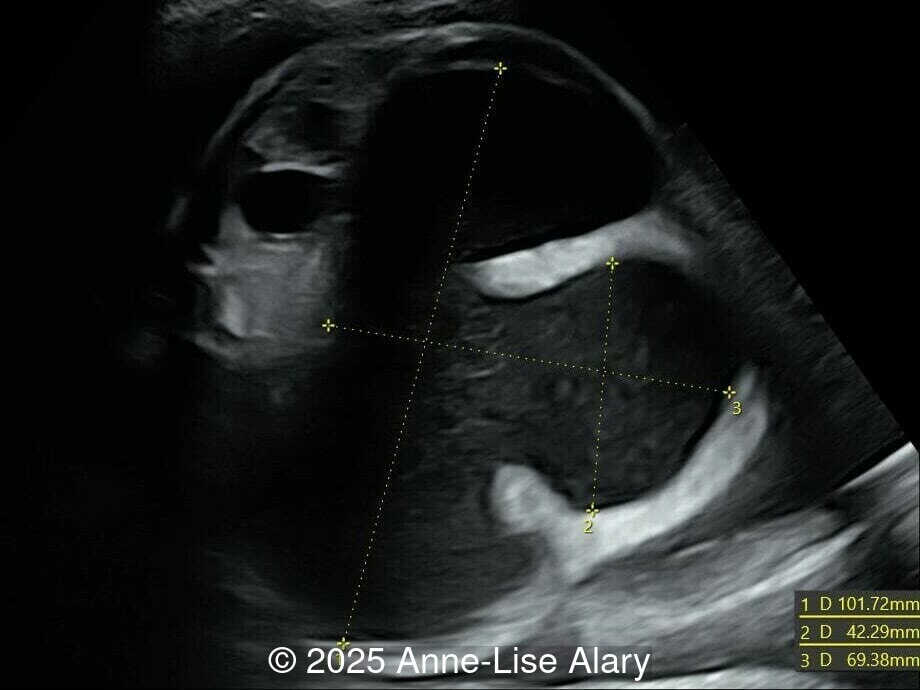

Axial image of the abdomen

Image 1 Axial image of the abdomen

Our prenatal ultrasound revealed a male fetus with megabladder, dilation of both ureter and kidneys, and thinned kidney parenchyma consistent with Lower Urinary Tract Obstruction (LUTO).  Additional findings suspected on ultrasound and confirmed on computed tomography included: